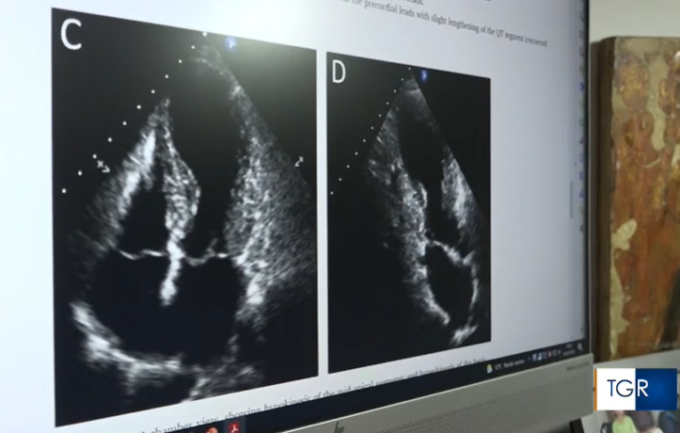

I ricercatori che hanno descritto per primi la sindrome di Takotsubo hanno ritenuto di dare questo appellativo alla sofferenza in questione poiché, come approfondito successivamente, alle immagini ecocardiografiche o di risonanza magnetica il ventricolo sinistro del paziente assume una forma del tutto simile al takotsubo per la pesca dei polpi. La causa precisa della sindrome di Takotsubo è a tutt’oggi poco chiara.